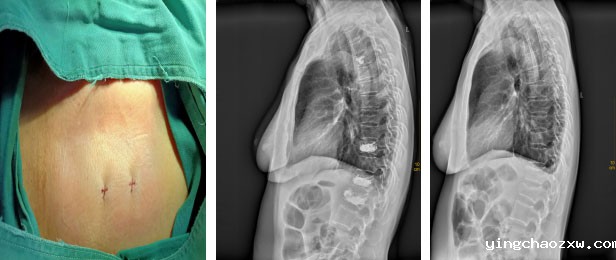

主要收治骨外科、神经外科、创伤外科、烧伤外科、血管外科患者,先后开展人工髋关节置换术、膝关节置换术、人工肩关节置换术、人工膝关节单髁置换术、髋关节感染病灶清除Spaecr植入术、下肢深静脉栓塞滤器植入术、下肢深静脉栓塞经皮导管溶栓术、膝关节关节镜下清理、半月板缝合、交叉韧带重建术、脊柱内镜下椎间盘摘除术、颈腰椎间盘突出椎管减压融合术,腰椎管狭窄、腰椎滑脱椎管减压术、融合术,脊柱骨折内固定术、椎体成形术(PKP、PVP)等多项现代医疗技术及骨盆骨折、四肢创伤骨折、脱位等手术。近年来,外二科各项现代医疗技术不断涌现,先后开展了外周血管介入手术、椎间孔镜下椎间盘摘除术、(MIS-TLIF)微创椎间融合术治疗腰椎间盘突出症、神经介入手术、脑出血微创治疗、脑膜瘤切除术等新技术。

经皮椎体成形术